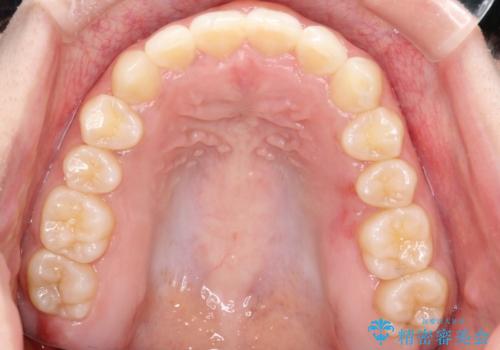

押しつぶされた歯列、アーチの拡大だけで非抜歯で改善した症例

強い叢生がありましたが、抜歯は行わず上下顎ともに、主に歯列弓の拡大を行い叢生を改善しました。

見た目、嚙み合わせ及び、治療期間や施術内容に大変ご満足いただきました。